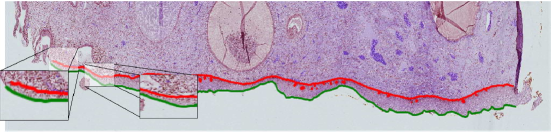

In Fig. 5, the red line corresponds to the coordinate information of the BM, while the green line corresponds to the coordinate information in the upper membrane. Determining the basal and upper membrane coordinates allows to know in which region of the epithelium the cells are located. After the region of interest (squamos epthitelium) has been obtained, an interface developed within the scope of the study is used to divide the whole epithelium to SEP which can be assumed equal in length (see Fig. 6).

The image patches which are analyzed in this study are represented in Fig. 6. The coordinates of basal and upper membranes of the epithelium are marked by the pathology experts with the use of a graphical interface. Coordinates data information of the papillae which represented with yellow line are also stored in separated files.